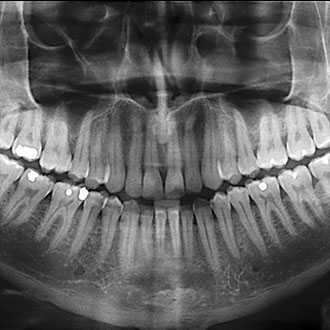

An OPG (Orthopantomogram) is a scan that gives a panoramic view of your jaw and teeth. The scan can provide information on wisdom teeth, bone loss, orthodontic assessment, jaw trauma, dental pain, or be used as part of a general dental check-up.

OPG. An OPG is a panoramic or wide view x-ray of the lower face, which displays all the teeth of the upper and lower jaw on a single film. It demonstrates the number, position and growth of all the teeth including those that have not yet surfaced or erupted.